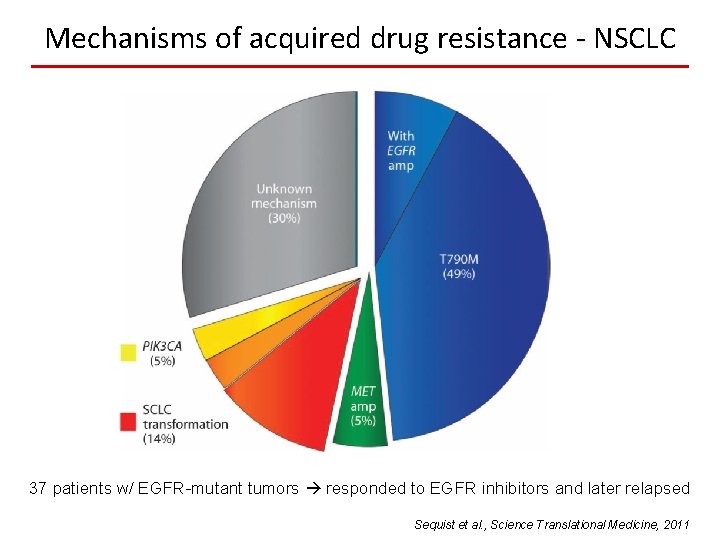

Mechanisms of acquired drug resistance - NSCLC 37 patients w/ EGFR-mutant tumors responded to EGFR inhibitors and later relapsed Sequist et al. , Science Translational Medicine, 2011